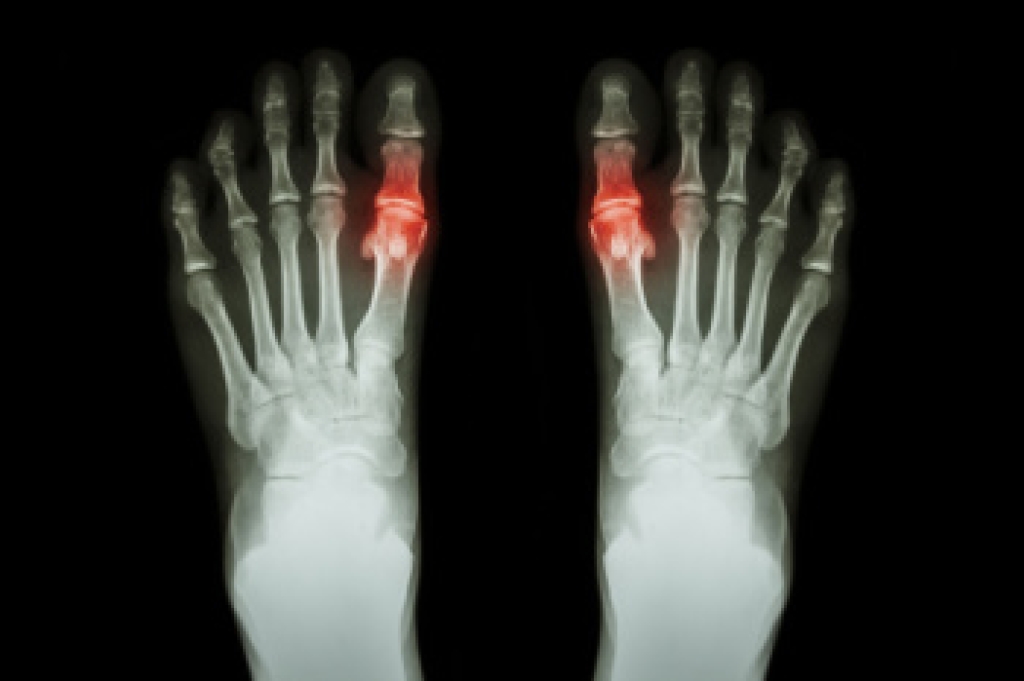

Those with diabetes are at serious risk due to being unable to feel an ulcer on their feet. Diabetics usually also suffer from poor blood circulation. This can lead to the wound not healing, infections occurring, and the limb may have to be amputated.